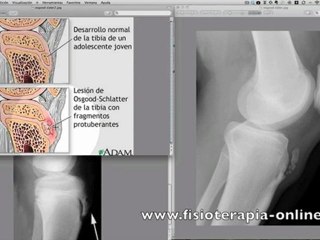

Equipe de France : Maladie de Sever, d'Osgood-Schlatter... Un joueur pas épargné par les soucis de s

Actu Star: Merci beaucoup d'avoir regardé!br Si vous souhaitez plus de nouvelles, abonnez-vous à la chaîne!br CLIQUEZ ICI POUR INSCRIRE: br Equipe de France : Maladie de Sever, d'Osgood-Schlatter...